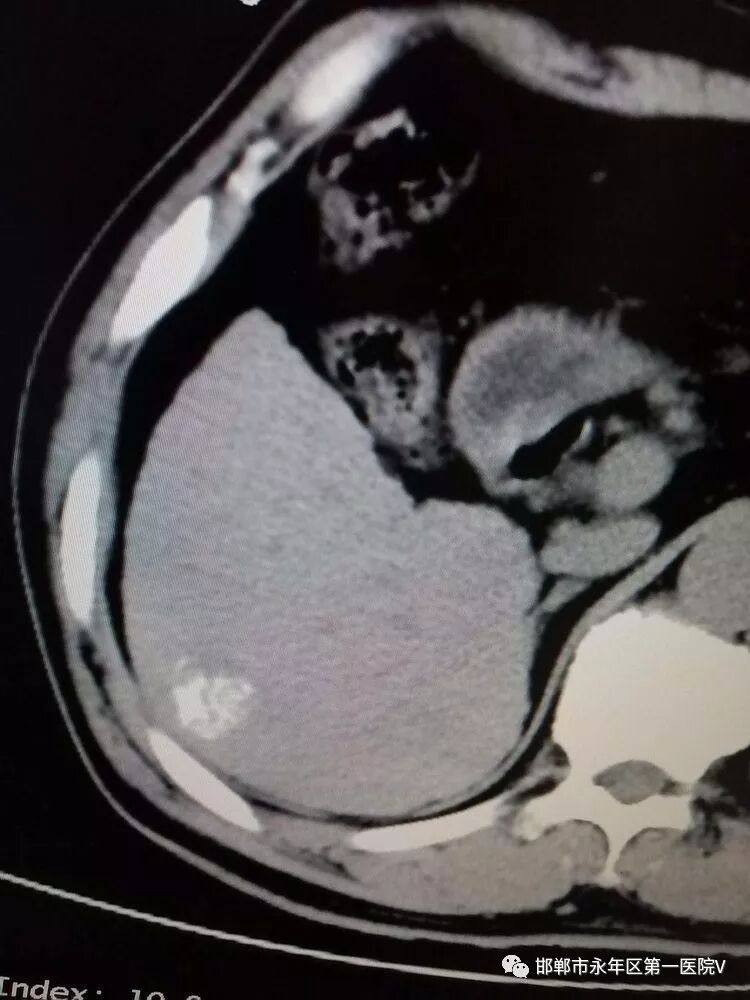

行2次叠加消融达到完全根治肿瘤的目的,术后扫描可见肿瘤完全坏死及周边安全范围低密度晕,手术成功!!!